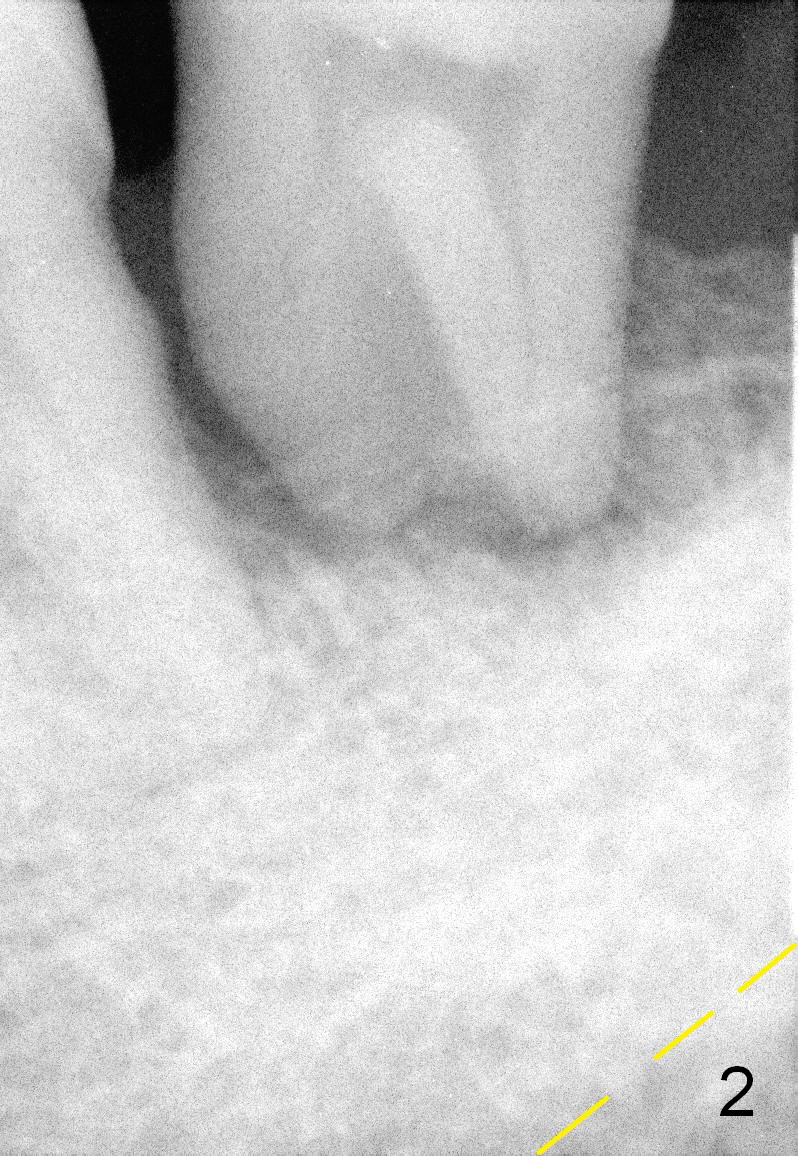

A 63-year-old man has periodontitis. The tooth #18 (probably 17) has mobility III (Fig.1). Three more PAs are taken with deeper placement of #2 sensor (Fig.2,6,7) to show the upper border of the Inferior Alveolar Canal (yellow dashed lines). The affected tooth has severe bone loss, especially mesially (Fig.2,3 (arrowheads)). No matter whether bone (Fig.4) or gingiva (Fig.5)-level implant is placed, the threads should be covered circumferentially by bone, native or grafted (red circles). In Fig.5, the threads are apical to black arrowheads, whereas the rough surface, which should be also contacted by bone, is the lower half above the black arrowheads.